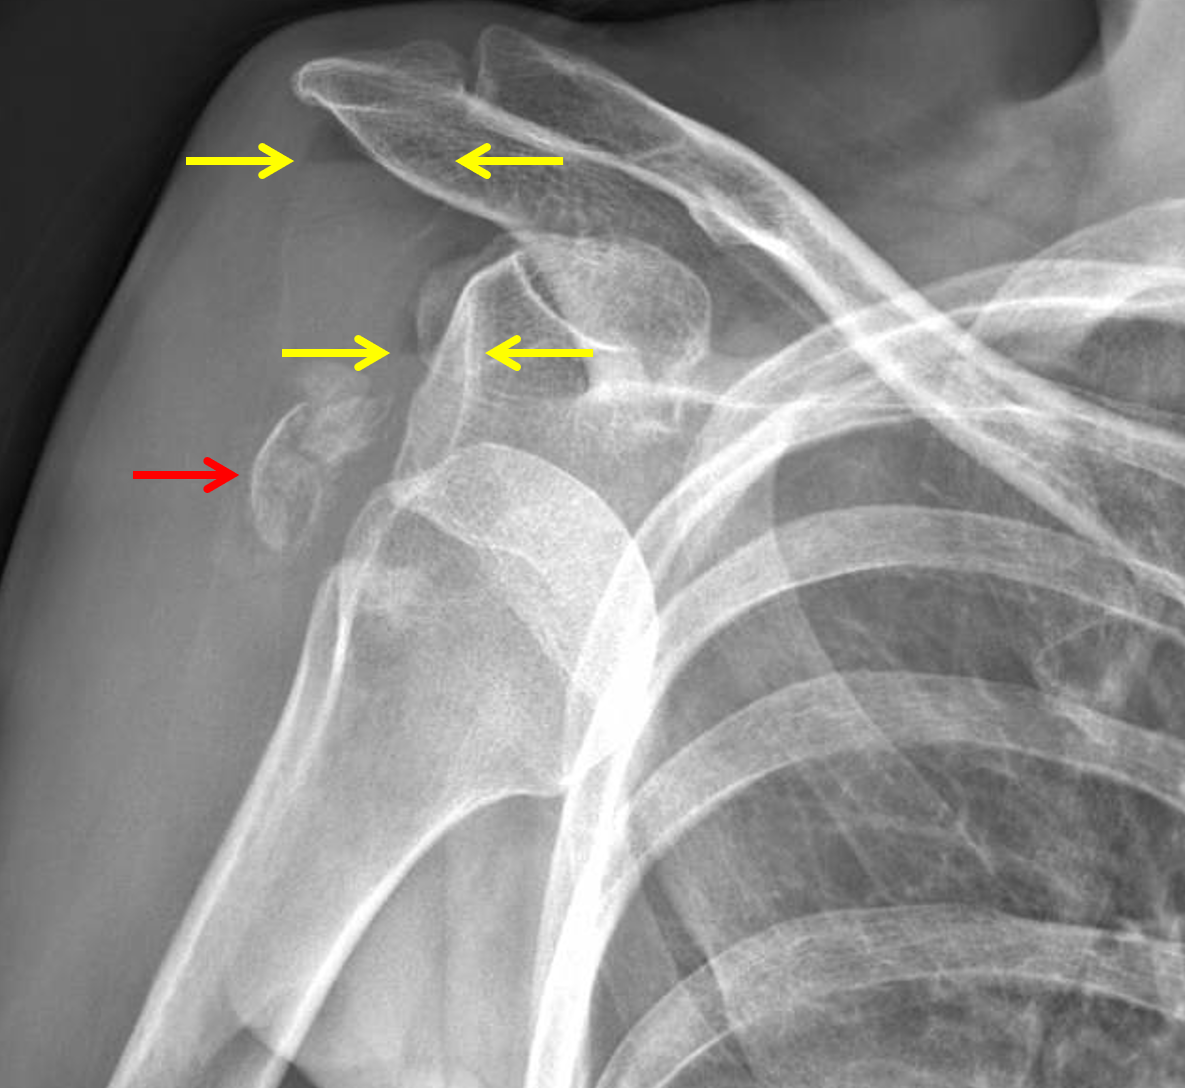

Shoulder Dislocation With Fracture Bathing With A Broken Shoulder You may find comfort if you prop your injured arm up with a pillow while you’re sitting on your couch or lying in bed. Using soaps in a pump container make the bathing process easier with just one arm. You know you have to wear your sling to protect your shoulder after your operation but you need to shower. This. Bathing With A Broken Shoulder.